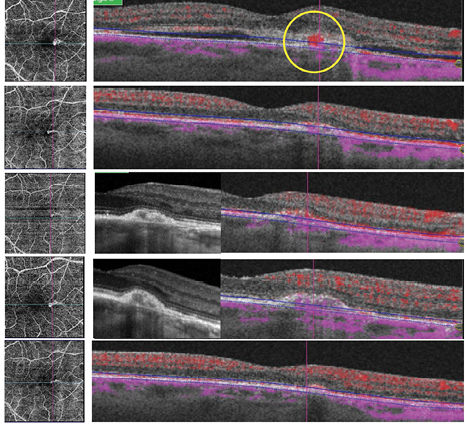

Multimodal imaging of type II CNV shows leakage on fluorescein angiography (FA), and indocyanine green angiography (ICGA) eliminates retinal angiomatous proliferation (RAP) or polypoidal choroidal vasculopathy (PVC). Structural OCT-B shows pigment epithelial detachment (PED) and subretinal hyper-reflective exudation (SHE) on high resolution. Topcon OCTA gives a wonderful hyper signal in a few seconds with good tracking.

This technology enables us to recognize type II CNV based on the appearance of dense branching and numerous tiny capillaries with a complete peripheral vascular arcade. Hemorrhages are detectable on color images, fluid is visible on the OCT-B scan, and leakage is visible on the fluorescein angiograph (FA). The imaging modalities are all included in the complete version of Topcon’s SS-OCT angiography. OCTA allows complete description of the CNV activity and CNV type.

Figure. Anti-VEGF injection plan based on OCTA quantitative information.

In routine practice, when patients ask if a treated lesion is still active, we can respond by checking the criteria. If we have, for instance, a well-defined shape, few anastomoses, and partial peripheral arcade, the CNV is still active with three of five essential criteria corresponding to fluid persistence on OCT-B scan. A closer look at the still active hyper-signal on the OCT-B scan indicates no colorized flow, indicating that it is an inactive lesion. CNV activity offers diagnosis guidance, but OCTA enables a customized follow-up approach. We can adapt the rhythm of injections with more qualitative information (Figure). When improvement is seen at each follow-up visit, we can choose to treat and extend for longer periods. Evaluation of the findings in those types of cases provide a solid foundation for the decision to treat or not to treat.